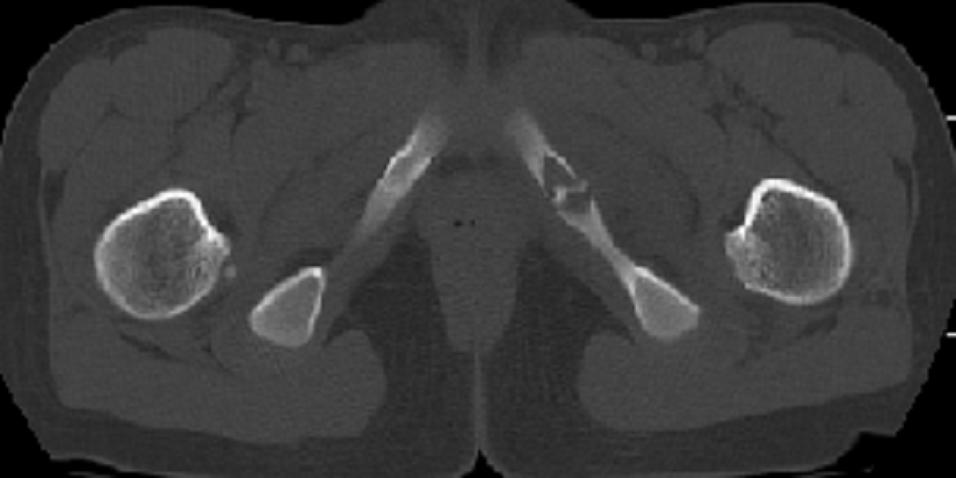

以下是引用zxd95在2008-7-2 10:06:00的发言:[br]左耻骨下支局部骨质破坏,内见小条状小骨片,周围肌间隙模糊,左闭孔内外肌肿胀。[br]儿童患者,首先考虑结核性,以骨质破坏为主(其内小条状小骨片解释为死骨)。[br]鉴别:[br]1、化脓性病变以增生为主;[br]2、肿瘤性病变:良性肿瘤不会有周围软组织的肿胀、模糊;恶性肿瘤病变骨皮质破坏、中断;[br]3、肿瘤样病变:一般也无周围软组织的改变。[br]建议查肺部及结核相关实验室检查。

以下是引用dyqct在2008-7-2 15:38:00的发言:[br]左坐骨与耻骨交界处膨胀性溶骨性病变,周围软组织略肿胀,边界不清。[br]发生在这个年龄组该部位最常见的一种发育变异,可以出现此种改变。另外感染不除外,建议定期复查。